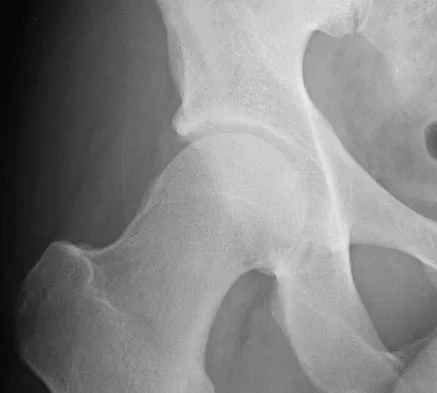

Figure 44 shows the radiograph of an 11-year-old girl who has hip pain. Further diagnostic workup should include

Explanation

The patient has severe acetabular protrusio, a condition that is frequently associated with Marfan syndrome. An echocardiogram is necessary to rule out the most serious consequence of this syndrome, aortic root widening, which can lead to aortic valve dysfunction or fatal aortic rupture. An electromyogram may be indicated for Charcot-Marie-Tooth disease, which is associated with acetabular dysplasia, but not protrusio. The renal ultrasound, the MRI scan, and the biopsy would be of no value in this patient. Protrusio can also be seen in patients with osteogenesis imperfecta and juvenile rheumatoid arthritis. Steel HH: Protrusio acetabuli: Its occurrence in the completely expressed Marfan syndrome and its musculoskeletal component and a procedure to arrest the course of protrusion in the growing pelvis. J Pediatr Orthop 1996;16:704-718.